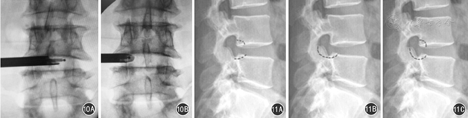

最初的脊柱内镜仅仅切除椎体后缘的纤维环,进入椎间盘和椎管,摘除脱出的纤维环和髓核。使用简式技术在治疗腰椎管狭窄症时,要切除或者磨除增生的上关节突前缘、黄韧带、上位椎体的下缘、下位椎体的上缘、后纵韧带、增厚肥厚的纤维环、退变的髓核组织从而达到椎管前方减压的治疗效果(图10,图11)。